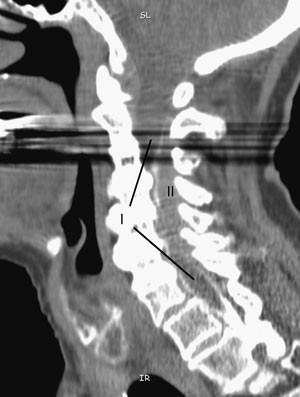

Lumbal spinalpunksjon ga blank spinalvæske med normal dråpetakt og normale verdier for celler, protein og glukose. Pasienten kunne ikke undersøkes med MR grunnet pacemaker. CT av cervikalcolumna viste ingen skjelettskade, men ga heller ingen forklaring på myelopati. Røntgenmyelografi med intratekal kontrast via lumbalt innstikk viste spinalt blokk i nivå C6 (fig 1). Etterfølgende CT avdekket en romoppfyllende prosess bak og til høyre for ryggmargen i samme nivå, som presset ryggmargen mot venstre (fig 2). Ved sagittal (fig 3) og koronal rekonstruksjon så man utstrekningen av prosessen opp til overgangen C2/C3.